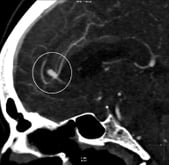

Angiotomografia perfil mostrando um aneurisma cerebral (círculo).

Angiotomografia 3D projeção perfil revelando um aneurisma cerebral (círculo).